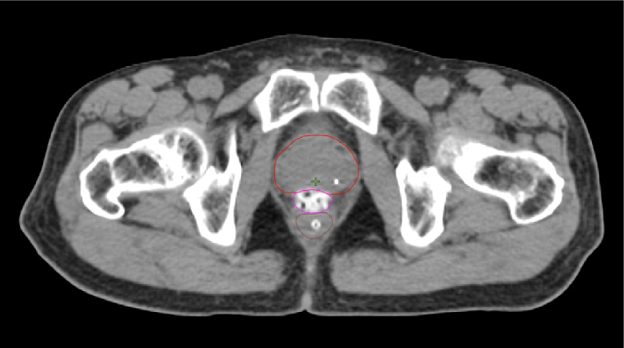

SpaceOAR-CT image.

A. SpaceOAR-CT

SpaceOAR-T2 MRI image.

B. SpaceOAR-T2 MRI

SpaceOAR Vue-CT image.

C. SpaceOAR Vue-CT

SpaceOAR Vue-T2 MRI image.

D. SpaceOAR Vue-T2 MRI

Figure 1. SpaceOAR Hydrogel vs. SpaceOAR Vue Hydrogel on CT and 1.5T T2 MRI simulation scans. Representative axial CT and T2 MRI simulation scan images from two patients who received perirectal hydrogel spacer with SpaceOAR Hydrogel (A, B) or SpaceOAR Vue Hydrogel (C, D). For SpaceOAR Hydrogel (A, B) hydrogel was contoured on MRI and modified based on CT, whereas for SpaceOAR Vue Hydrogel (C, D) hydrogel was contoured directly on the CT simulation scan. Note that for SpaceOAR Hydrogel (A, B) the T2 MRI hyperintense region in B between the prostate and rectal contours is not easily seen on CT in A. For SpaceOAR Vue Hydrogel, the hyperintense region on the T2 MRI in D corresponds to the hyperdense region between the prostate and rectum on CT in C. Red- prostate contour, Magenta- hydrogel contour, Brown- rectal contour.